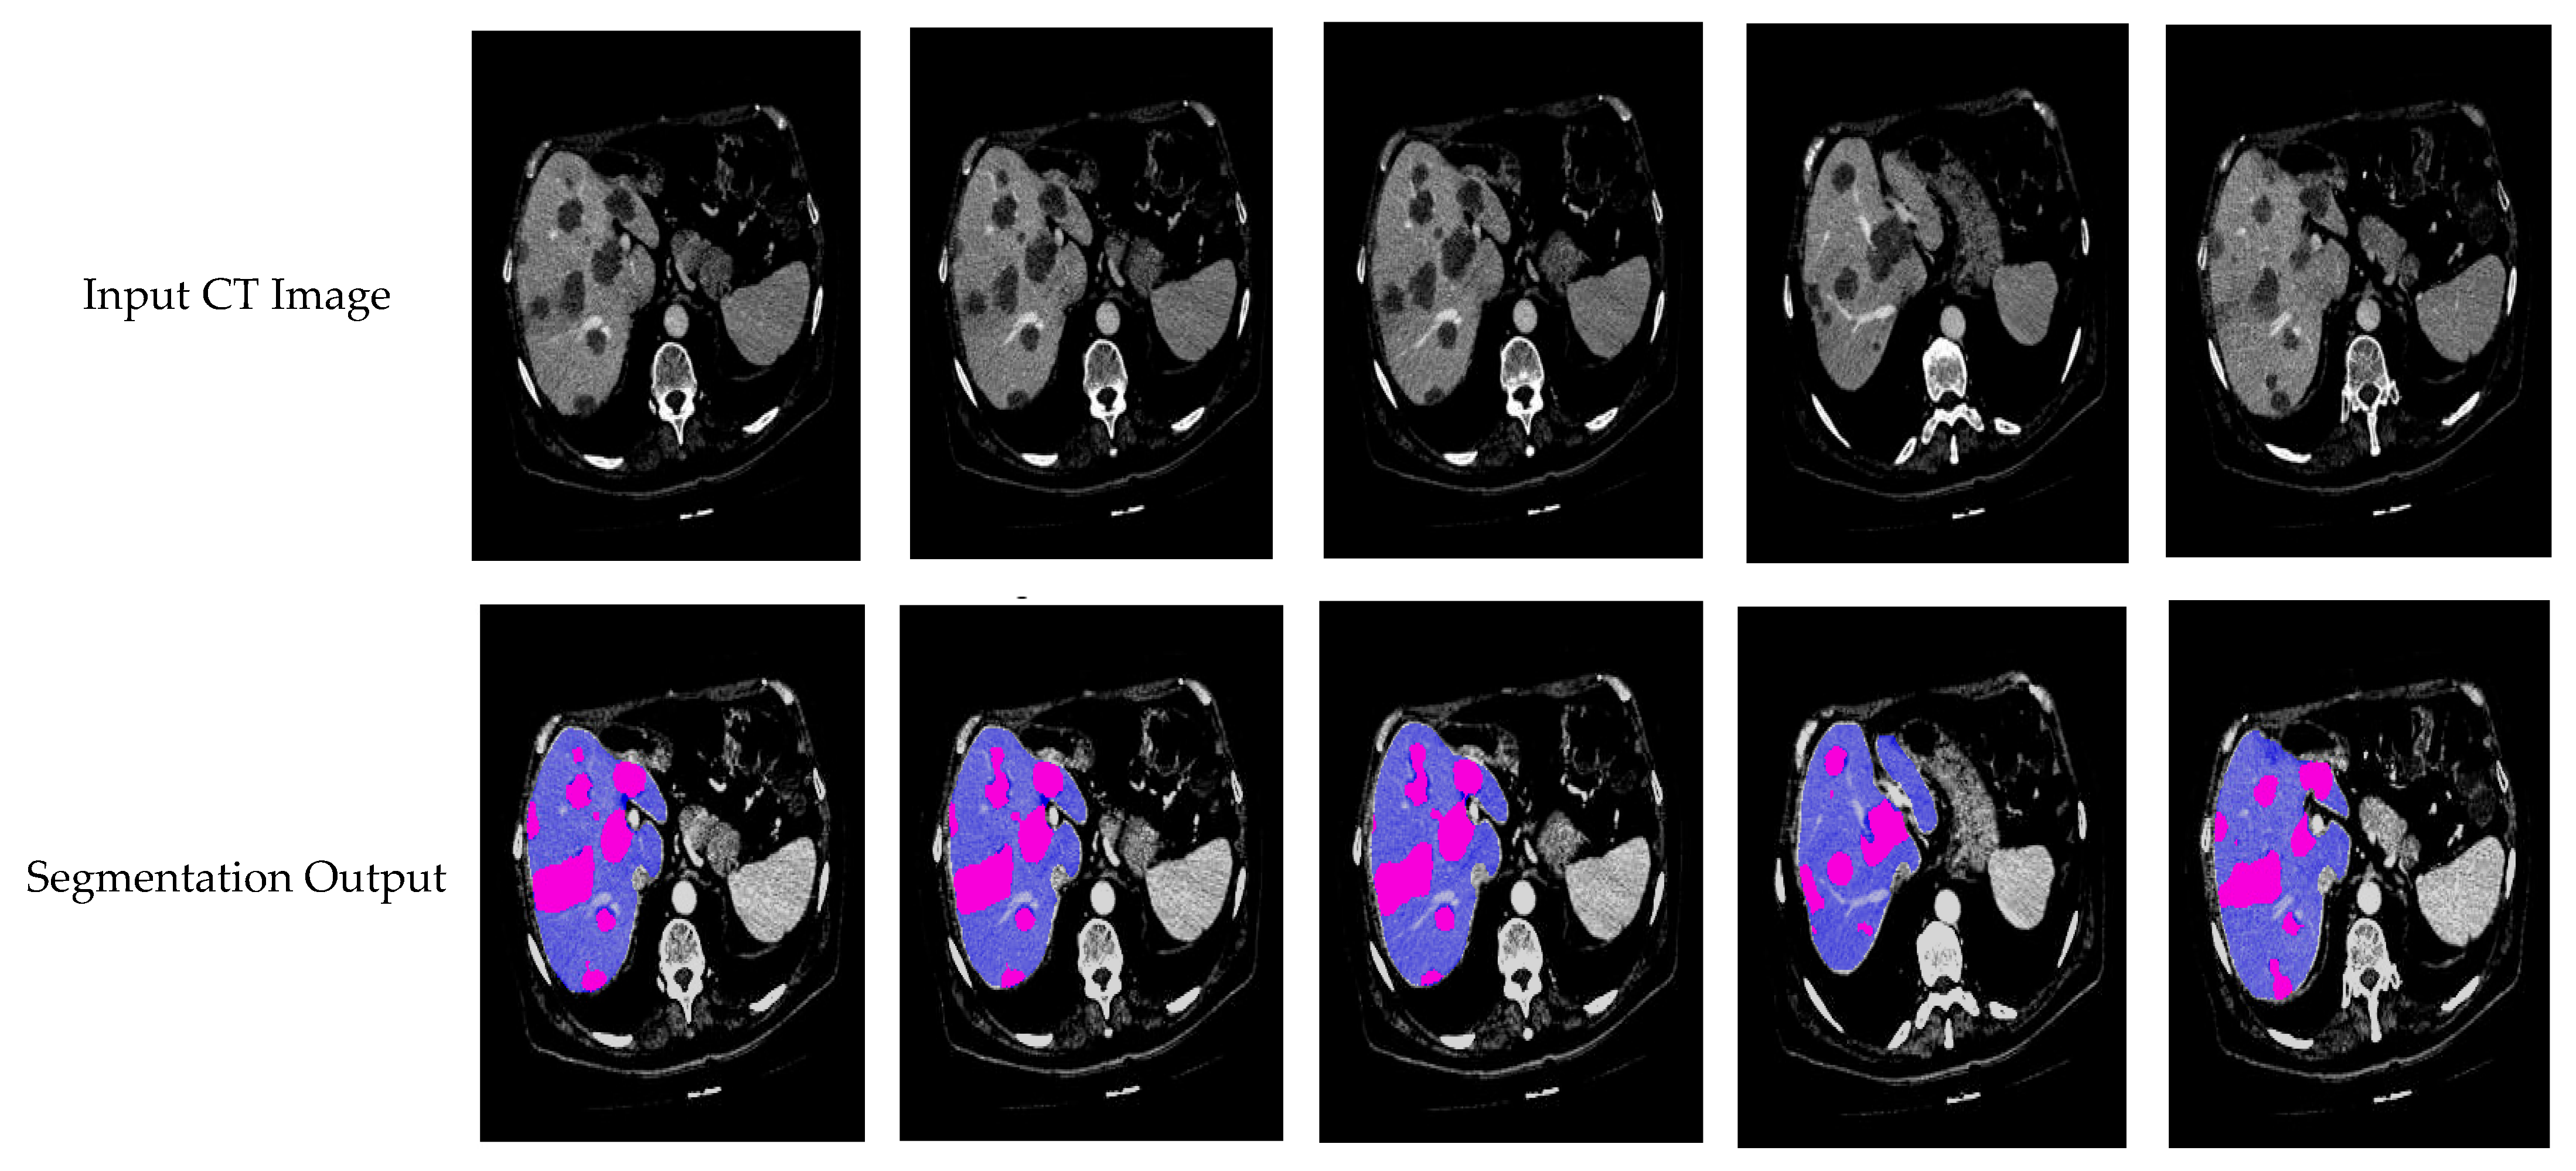

The segmentation results accurately depict the edges of the liver and tumor regions, which is crucial for defining the shape and size of these structures. The segmented areas closely align with the ground truth images, ensuring that the boundaries of the liver and tumor are well defined. This precise outlining indicates that the segmentation process was performed accurately, with no significant deviations from anatomical features. In Figure 9, the liver is shown in red, while the tumor is highlighted in yellow. Both regions are detected smoothly, without abrupt changes, demonstrating the effectiveness of the proposed system in identifying and segmenting the liver and tumor.

In Figure 10, a comparison is presented between the input images and their corresponding segmentation results. The liver is visually represented in purple, while the tumor is highlighted in pink. The segmentation results demonstrate the algorithm’s effectiveness in accurately identifying and distinguishing between the liver and tumor regions within the CT images. This visual analysis underscores the robustness of the proposed method in handling complex anatomical structures.

Figure 9. Segmentation output of proposed model for 3DIRCADb dataset.

Figure 10. Visual segmentation results of proposed model.